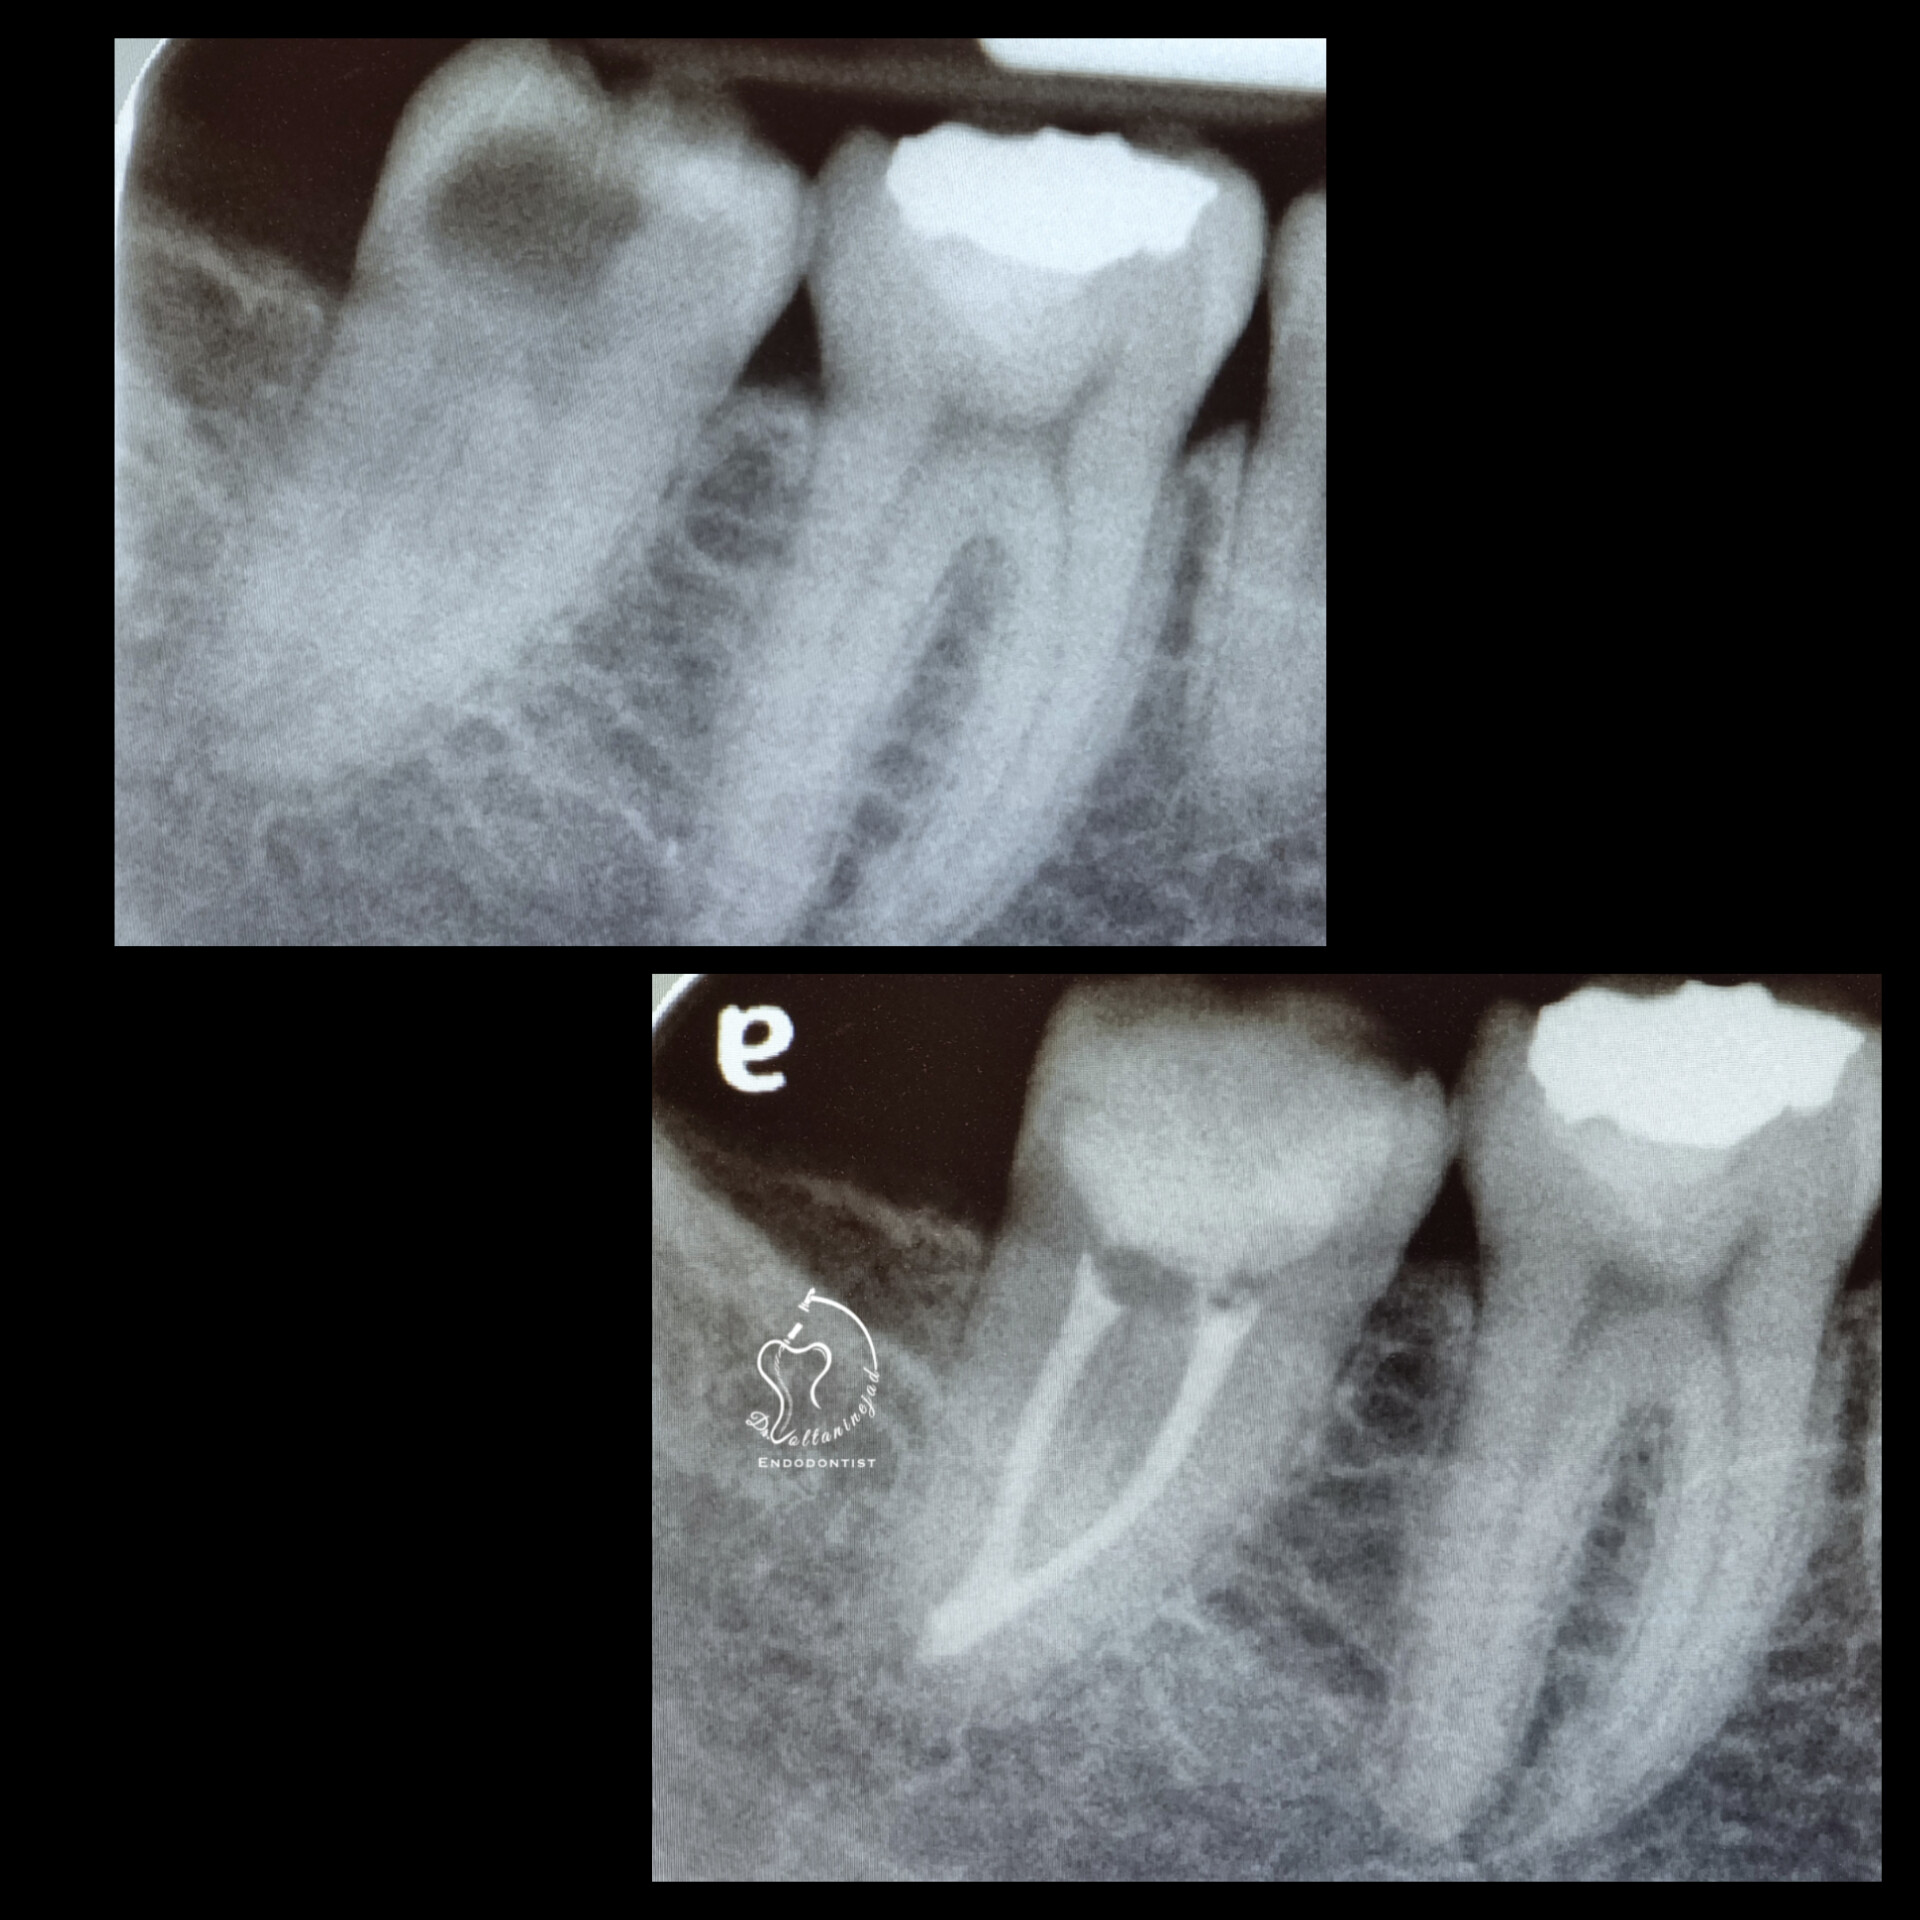

🔹 خارج کردن فایل شکسته از کانال

• شرح کوتاه: بیمار با درمان ریشه نامناسب و فایل شکسته در کانال مراجعه کرد. فایل با میکروسکوپ خارج شد و درمان ریشه مجدد انجام شد.

• نتیجه: رفع درد و حفظ دندان بدون نیاز به جراحی.

خارج کردن فایل شکسته

🔹 درمان ریشه مجدد (Retreatment) در دندان پرمولر

• شرح کوتاه: درمان قبلی نامناسب و همراه با عفونت بود. درمان مجدد با میکروسکوپ انجام شد.

• نتیجه: ترمیم ضایعه استخوانی و بازگرداندن دندان به شرایط سالم.

درمان ریشه مجدد پرمولر